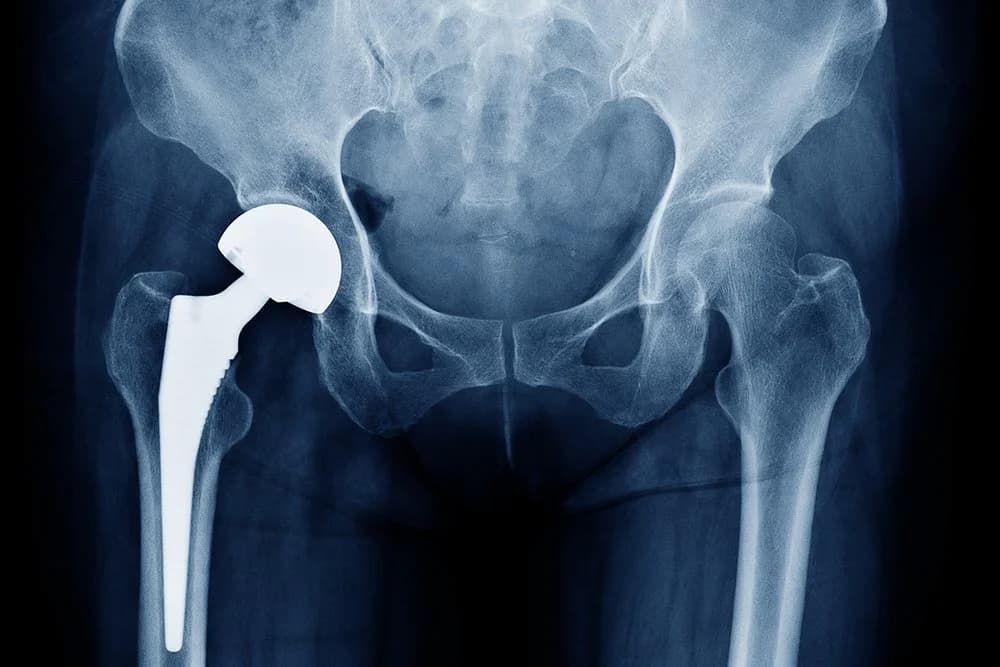

A hip replacement is a surgical procedure in which the damaged parts of the hip joint are removed and replaced with a prosthesis designed to replicate the ball‑and‑socket mechanics of a healthy hip. In a total hip arthroplasty the surgeon replaces both the femoral head (the ball) and the acetabular socket; a hemiarthroplasty replaces only the femoral head in select fracture cases. Implants are typically made from combinations of metal, ceramic, and high‑density polyethylene to provide durable, low‑friction motion. The operation is indicated when hip pain and stiffness significantly limit daily activities and conservative measures—such as medications, physical therapy, weight management, and injections—no longer provide adequate relief. Surgeons choose an approach and fixation method (cemented, uncemented, or hybrid) based on patient age, bone quality, and activity level; uncemented components rely on bone ingrowth into a porous surface, while cemented components are fixed with bone cement. The procedure usually takes one to two hours under regional or general anesthesia, and most patients begin mobilizing with physical therapy within 24 hours. Modern hip replacements can last many years, often 15 years or more, but implant longevity depends on activity, implant type, and surgical technique.

A total hip replacement (total hip arthroplasty) replaces both the femoral head (ball) and the acetabular socket with prosthetic components and is the most common option for end‑stage arthritis because it reliably relieves pain and restores function; implants may be cemented, uncemented, or hybrid depending on bone quality and surgeon preference.

Choosing the best hip replacement implant depends on individual goals and biology rather than a universal winner. Modern implants combine a femoral stem, a ball (head), and an acetabular liner or cup, and are made from metal, ceramic, and high‑density polyethylene in various pairings to balance wear resistance, strength, and biocompatibility. For many patients metal‑on‑polyethylene and ceramic‑on‑polyethylene bearings offer a reliable mix of durability and low wear, making them common first‑line choices because they perform well across ages and activity levels. Ceramic‑on‑ceramic bearings have very low wear but carry a small risk of squeaking and are chosen selectively for younger, active patients who prioritize longevity. Hip resurfacing preserves more bone and can suit some younger men with good bone quality, but it has fallen out of favor for many because of specific metal‑related risks and fracture concerns. Fixation method—cemented, uncemented, or hybrid—is equally important: uncemented implants rely on bone ingrowth and are often preferred in younger patients with good bone, while cemented stems may be better for older patients with poor bone quality. Ultimately, the best implant is the one that matches your anatomy, lifestyle, and long‑term plan, chosen in partnership with an experienced surgeon.